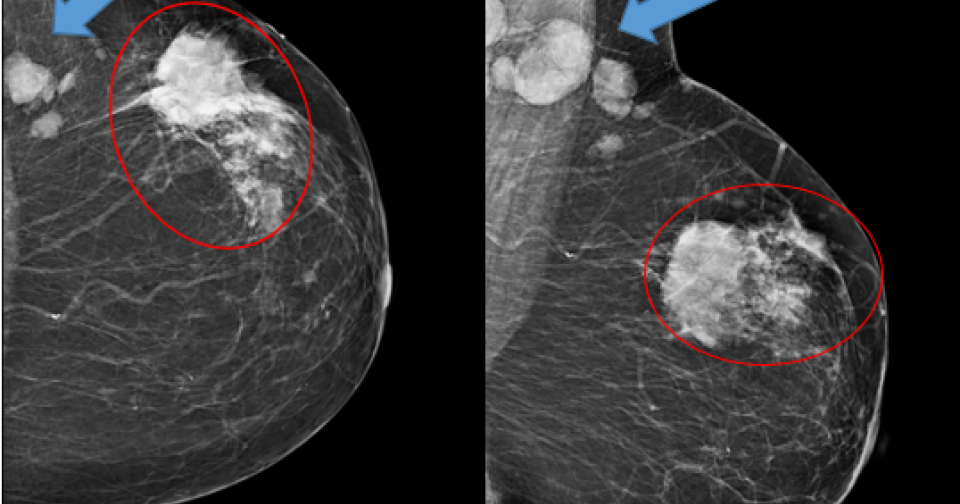

Узи молочной железы birads 3 123 фото